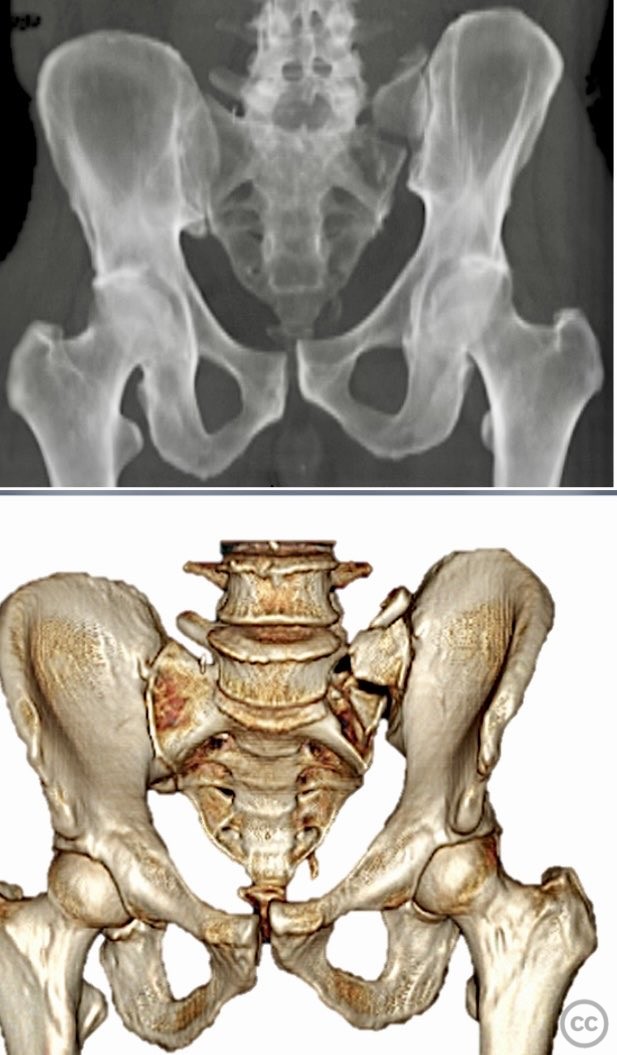

Clinical and radiological findings:  Middle-aged male involved in a motor vehicle accident sustained a complete symphysis pubis (SP) disruption and left sacroiliac (SI)/sacral combination fracture-dislocation (AO/OTA 61-C1.3). The patient presented with an open traumatic posterior pelvic wound. Initial assessment revealed hemodynamic instability requiring urgent laparotomy and subsequent angioembolization for pelvic hemorrhage. Axial CT imaging demonstrated significant displacement of the anterior and posterior pelvic ring, with embolic coils visible post-intervention.